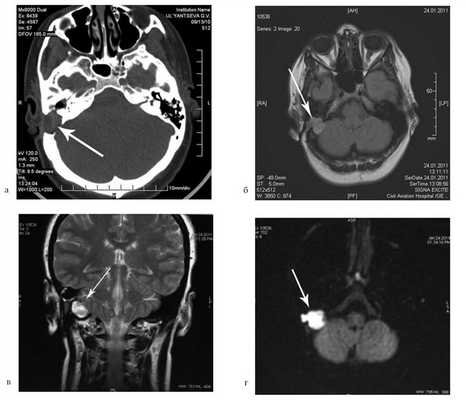

На КТ височных костей справа послеоперационная полость, заполненная мягкотканным образованием, определяется большой костный дефект в направлении сигмовидного синуса и мозжечка (рис. 2, а). Рисунок 2. КТ и МРТ височных костей больной У. с хроническим правосторонним средним отитом. Состояние после радикальной операции (1993 г.), санирующей операции с мастоидопластикой и тимпанопластикой (2003 г.). Холестеатома. Парез лицевого нерва. а — КТ; б — МРТ основания черепа в режиме Т1; в — в режиме Т2; г — в режиме non-EPI DWI.

Больной была выполнена МРТ (рис. 2, б—г).

В режимах Т2 и non-EPI DWI определяется сигнал высокой интенсивности, в режиме Т1 — низкоинтенсивный сигнал. Это может свидетельствовать о наличии холестеатомы мастоидальной полости и пирамиды височной кости. Диагноз: хронический правосторонний средний отит; состояние после радикальной операции в 1993 г. и санирующей операции с мастоидопластикой и тимпанопластикой в 2003 г.; холестеатома; парез лицевого нерва.